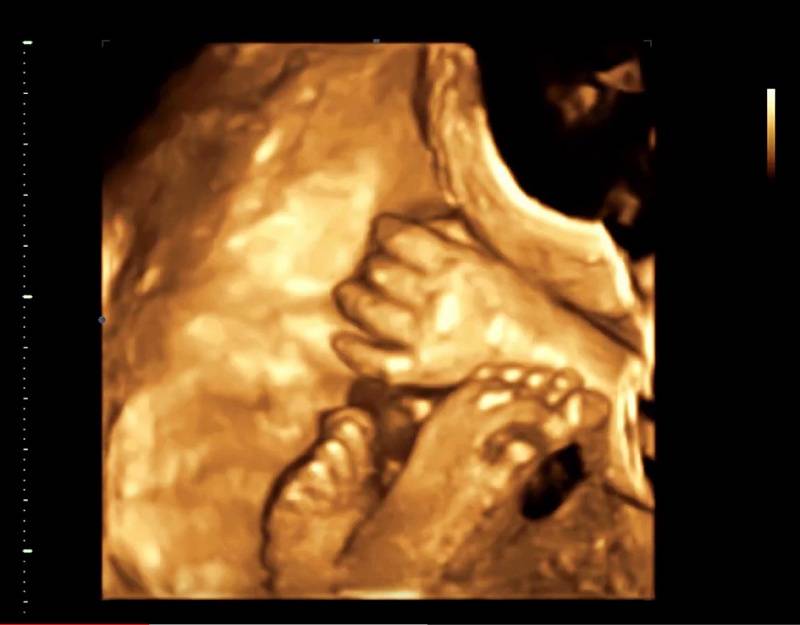

Существуют даже методики так называемого экологического ультразвука в первом триместре, когда после получения объемного фаила, все дальнейшее исследование с получением нужных 2-хкамерных срезов и измерения проводится виртуально на компьютере. По факту, такой метод даже сокращает время непосредственного воздействия ультразвука на эмбрион. Хотя, конечно, большинству, 3D режим знаком по функции поверхностной реконструкции, когда можно получить красивые фотографии лица плода.

4D режим представляет из себя 3D режим в реальном времени. Для пациентов это, в основном, пойманная во время исследования улыбка или, например, процесс зевания. Для врачей 4D – это наглядные движения в суставах кистей, стоп, и конечно, большой функционал при оценке функции сердца плода. Сердце – объемный и подвижный орган. Того уровня его оценки, который можно получить в 4D режиме, совокупностью 2-хмерных срезов добиться невозможно.

Нередко молодые родители записываются на такую процедуру добровольно. Она позволяет увидеть ребенка и даже некоторое время понаблюдать за ним: за движениями, мимикой. Кроме того, после процедуры родители получают первую портретную фотографию ребенка. Но для этих целей процедуру следует проводить на достаточно поздних сроках, после 22 недели. К этому моменту ребенок успевает полностью сформироваться.

При проведении 4D УЗИ можно увидеть движения плода, его лицо, руки, ноги и другие детали. Это позволяет родителям узнать больше о своем будущем ребенке и создает возможность для более раннего выявления возможных аномалий и отклонений.

4D УЗИ позволяет получать то же самое объёмное изображение, но уже в режиме реального времени. Благодаря усовершенствованным технологиям картинку можно поворачивать под разными углами и наблюдать, как ребёнок двигается в матке, улыбается, шевелит ручками и ножками. В этом и заключается разница между 3D и 4D УЗИ. В первом случае картинка объёмная и яркая, но статичная. Во втором – реальное объёмное изображение плода. 4D рекомендуется делать с 20-й и по 33-ю неделю. Процедура занимает около 45 минут. Родители могут получить на руки видео на DVD-носителе.